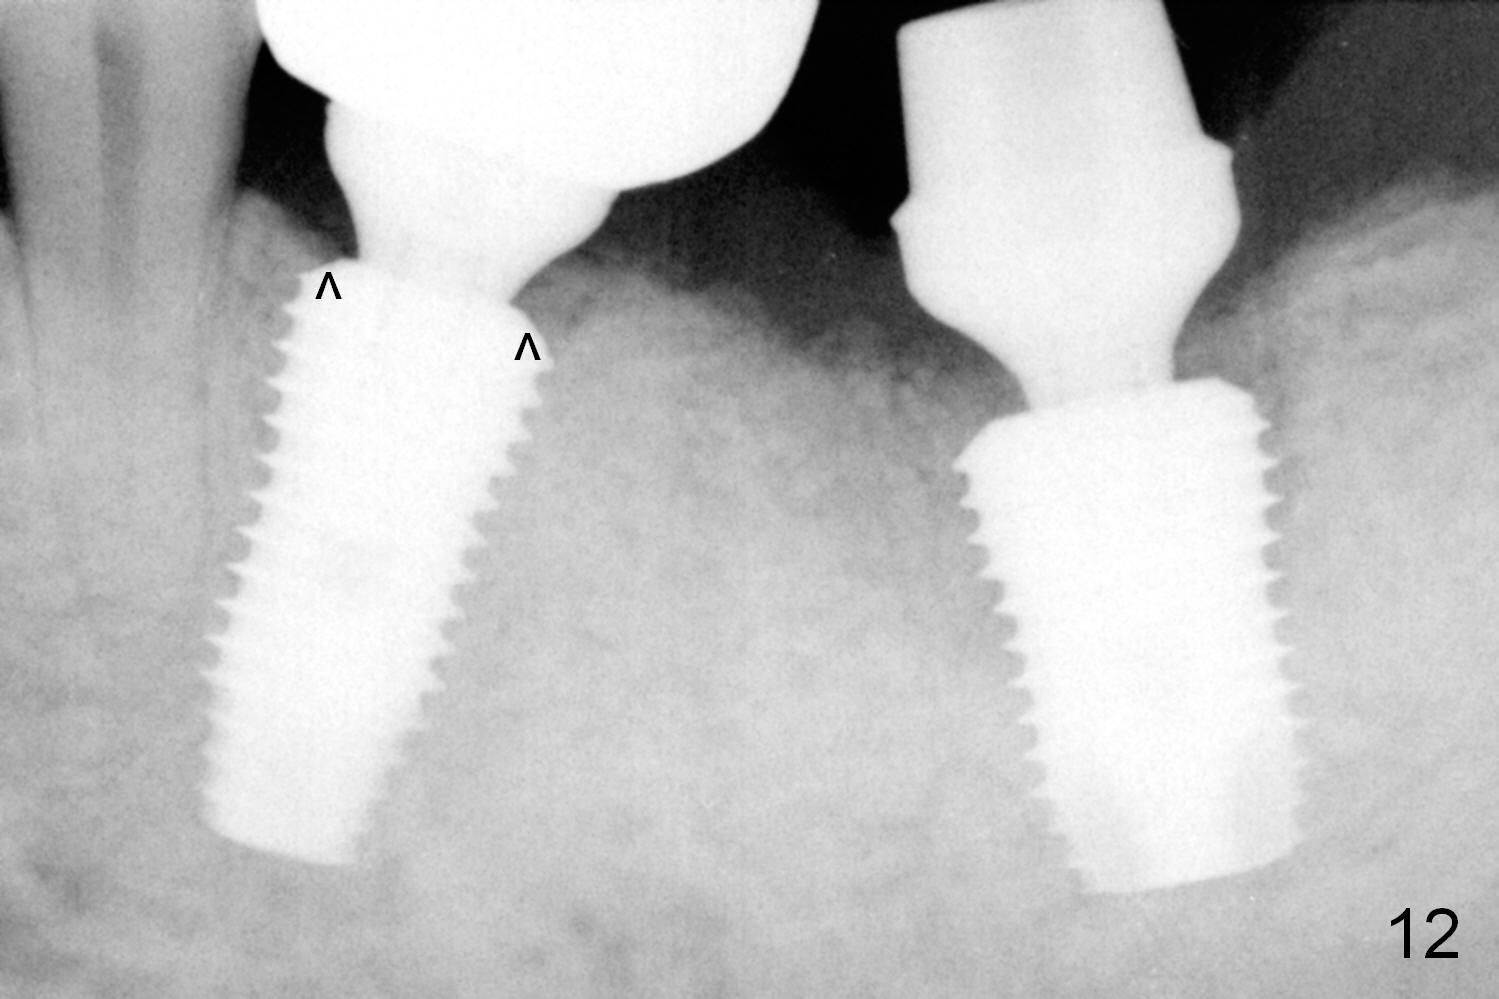

When the patient returns for final restoration 4 months postop, the soft tissue around the implant heals with distinct abutment margin (Fig.10). It is easy to take impression. This is due to the presence of the immediate provisional. The bone density in the original mesial (Fig.11 <) and distal (D) sockets increases, suggesting osteointegration. Eight months later (1 year postop (#19)), the tooth #18 becomes symptomatic and is extracted and replaced by an implant (Fig.12). The distal socket at #19 has disappeared, while the plateau of the implant is covered by the bone (^).